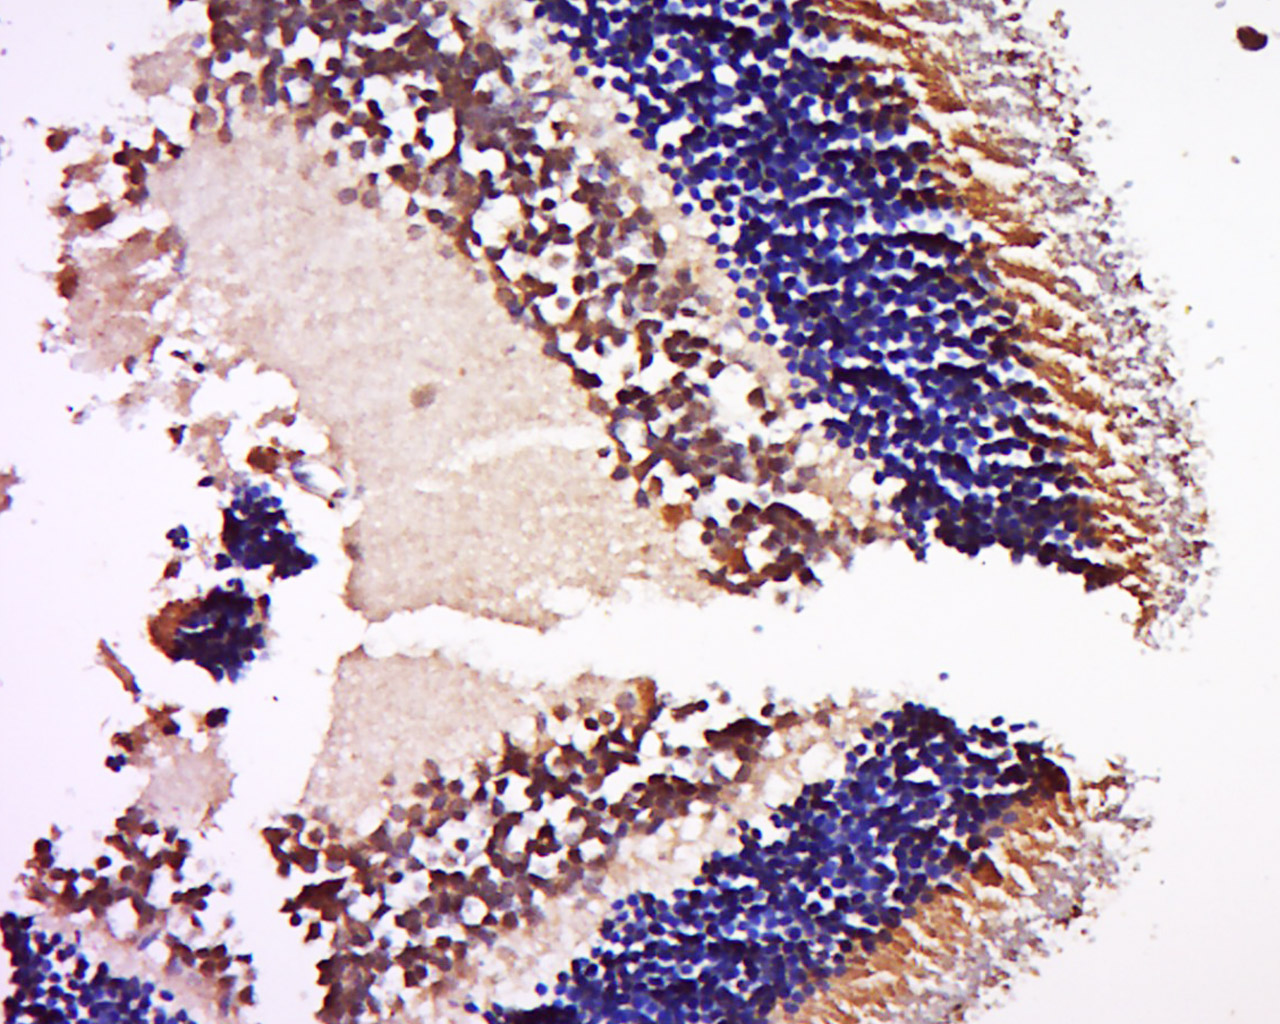

Antigen retrieval: citrate buffer ( 0.01M, pH 6.0 ), Boiling bathing for 15min; Block endogenous peroxidase by 3% Hydrogen peroxide for 30min; Blocking buffer (normal goat serum,C-0005) at 37∩ for 20 min;

Incubation: Anti-NRL Polyclonal Antibody, Unconjugated(bs-19351R) 1:500, overnight at 4∑C, followed by conjugation to the secondary antibody(SP-0023) and DAB(C-0010) staining